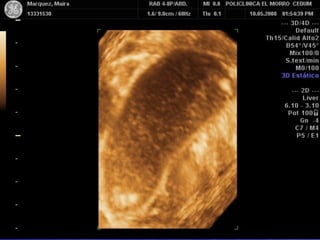

VARIANTES DE FORMA Y

CONGENITAS

• DE FORMA

Gorro frigio y presencia de pliegues

• CONGENITAS

Septos vesiculares verdaderos

Bilobulaciones

Anomalías de duplicación - dos componentes ( Funcional y

No Funcional)

Variante en gorro frigio

Variantes en gorro frigio

Pliegue de unión

Duplicación Vesicular